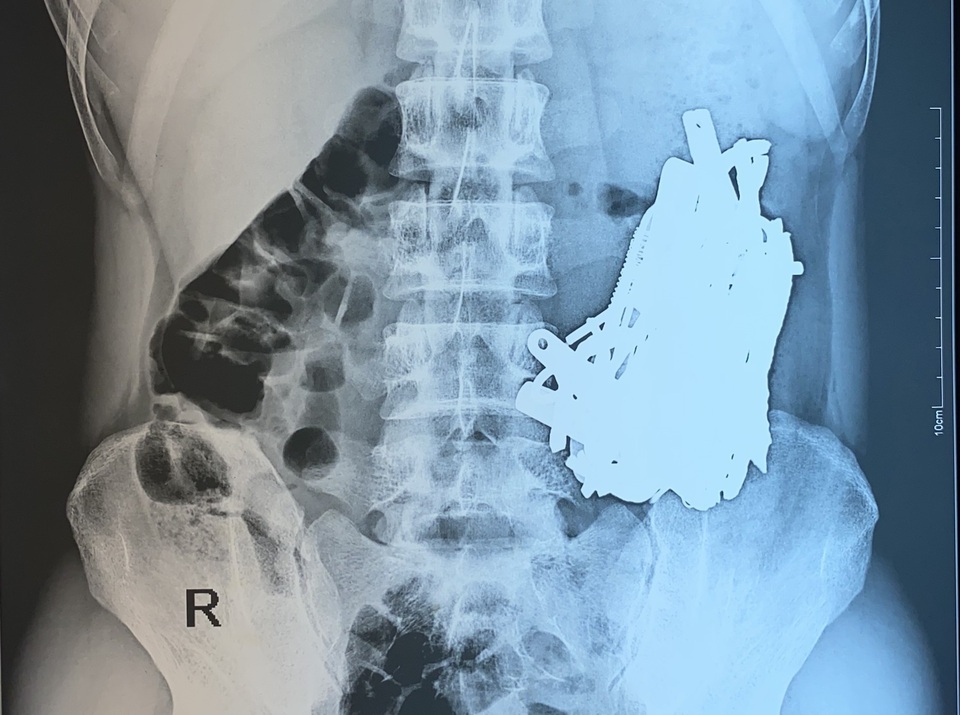

Trên kết quả kiểm tra hình ảnh, bác sĩ cũng "tá hỏa" khi phát hiện dạ dày bệnh nhân chứa đầy các vật cản quang có hình dạng khác nhau. Dị vật chất đầy trong dạ dày người bệnh nên không thể lấy ra bằng phương pháp nội soi. Ngay lập tức, bác sĩ chỉ định phẫu thuật cấp cứu cho bệnh nhân.

Bằng phương pháp mổ hở, bác sĩ đã mở ổ bụng, mở dạ dày lấy ra khoảng 1kg sắt thép các loại như đinh, thìa, bấm móng nay, lưỡi dao, thỏi sắt, móc đồ… đã bị dịch dạ dày ăn mòn. Do số lượng dị vật trong bụng bệnh nhân quá nhiều nên ê kíp phải tiến hành chụp C-ARM ( X-quang trong mổ) để tránh bỏ sót dị vật.